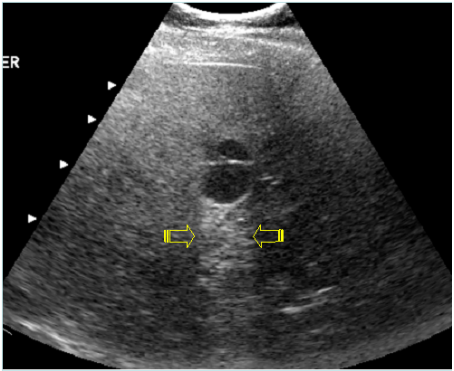

64.骨盆腔超音波掃描如下圖,箭號所指為何?

(A)膀胱 (B)攝護腺 (C)儲精囊 (D)直腸